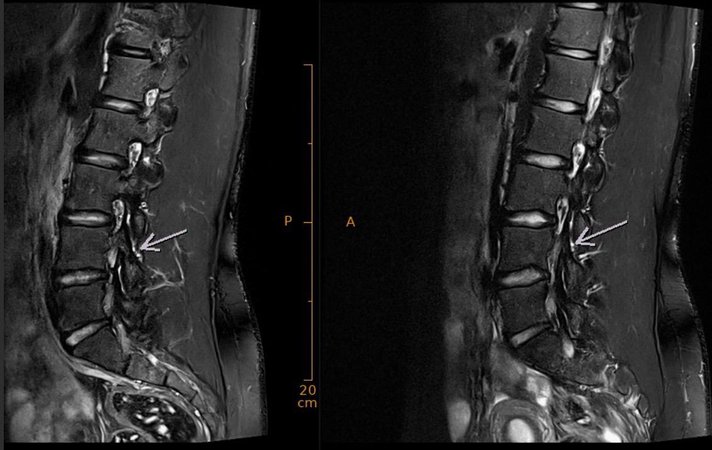

Depuis la mi-octobre, je traîne des douleurs au dos qui m’empêchent de m’entraîner sur les parcours de ski. J’avais déjà connu des douleurs la saison passée, qui étaient parties en juin, mais elles sont revenues lors des tests physiques à Macolin cet automne. Depuis, j’ai fait une IRM (photo), qui a confirmé une inflammation dans le bas du dos, accompagnée d’une forte tonicité musculaire. Les analyses ont aussi révélé une protrusion du disque intervertébral (plus d’info sur mon blog de novembre dernier).

Pour ce problème au dos, j’ai passé une IRM réalisée début novembre. Elle a révélé une inflammation dans le bas du dos, accompagnée d’une forte tonicité musculaire. Les analyses ont aussi révélé une protrusion du disque intervertébral (un disque intervertébral s’est déplacé hors de sa position normale, sans rupture de l’anneau fibreux, provoquant des douleurs, des engourdissements et une faiblesse musculaire en exerçant une pression sur les nerfs environnants). Après une semaine de repos et de soins, je remets les skis cette semaine après une petite pause de plus de deux semaines. Cette reprise sera tranquille, avec pour objectif de retrouver progressivement les sensations sans brusquer les choses.